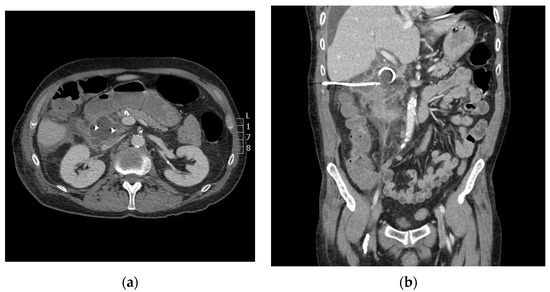

A 73-year-old male with a past medical history of ampullary neoplasm status post endoscopic ultrasound with fine needle aspiration and plastic biliary stent placement presents with right upper quadrant (RUQ) pain, elevated bilirubin, and leukocytosis two days after receiving endoscopic retrograde cholangiopancreatography (ERCP). Computed tomography (CT) of the abdomen revealed moderate free fluid adjacent to the extrahepatic biliary system, pancreatic head, and proximal duodenum (Figure 1). Blood cultures were negative. Repeat ERCP was performed, which showed biliary stent obstruction. The stent was removed and replaced with a 10 mm × 40 mm bare metal stent. Three days after the repeat ERCP, the patient reported worsening abdominal pain and CT showed an increase in RUQ simple fluid. A hepatobiliary iminodiacetic acid (HIDA) scan was performed to rule out biliary leak, which was negative. Due to the patient’s worsening leukocytosis, a repeat CT was performed which showed interval increase, organization, and hyperenhancement of a periduodenal collection. The patient therefore underwent CT-guided drainage of the collection with moderate sedation, which ultimately grew yeast (Figure 2a).

Figure 1. Axial computed tomography (CT) image shows moderate free fluid adjacent to the extrahepatic biliary system, pancreatic head, and proximal duodenum. Note the normal appearance of the left adrenal gland (red arrow).

Figure 3. Axial (a) and coronal (b) computed tomography (CT) imaging shows periduodenal drain placement with a 10 French catheter.